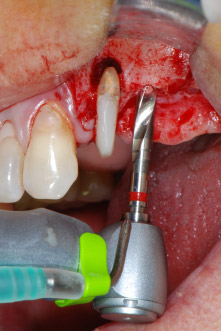

However, we maintained our initial plan to retain both teeth as temporary bridge abutments during the six-months osseointegration period of the implants. At reentry, the situation would have to be reassessed. First, in an attempt to manage the endo-perio problem, the remaining root surface was carefully debrided with piezoelectric equipment (Piezomed, W&H, used with the spatula-shaped insert S1, originally designed for erosion of the lateral sinus wall) (Fig. 4).

periodontium

Fig. 4: To preserve the tooth as a temporary abutment, the periodontium was debrided with piezoelectric equipment …

buccal apex of tooth 24

Fig 5: ... and the buccal apex of tooth 24 was abraded with the same instrument (apicoectomy).